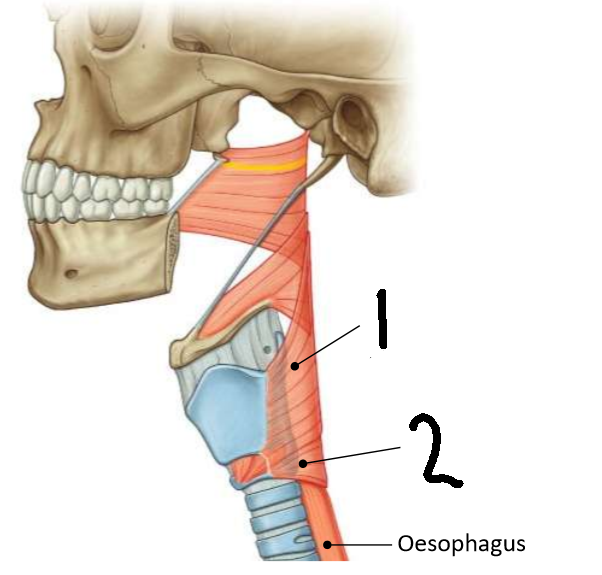

What muscle is this?

inferior constrictor

Which part of the muscle is 1?

thyropharyngeus

Which part of the muscle is 2?

cricopharyngeus

What are the attachments of this muscle?

oblique line of thyroid cartilage, cricothyroid tendon, cricoid cartilage → pharyngeal raphe